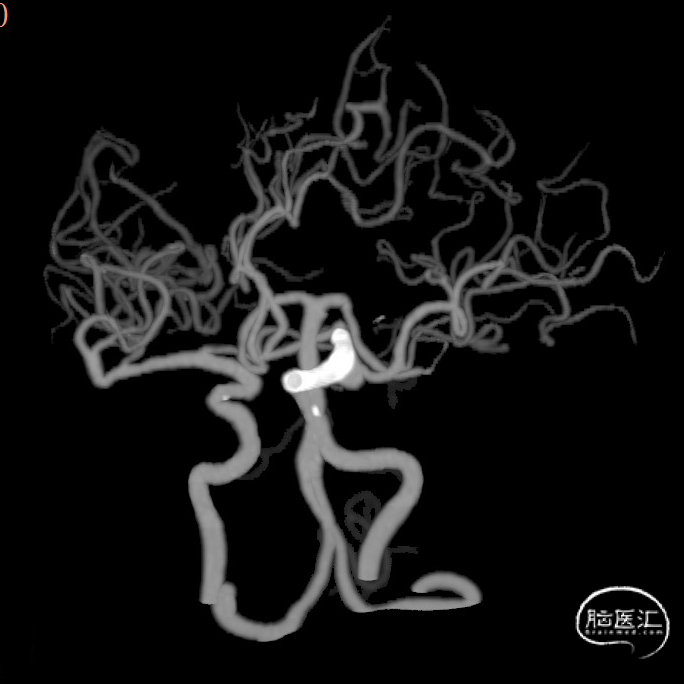

CTA:右侧颈内动脉C7段动脉瘤。

老年女性患者,检查发现右侧颈内动脉C7段大动脉瘤,动脉瘤直径大于10mm,形态不规则,宽颈,手术指征明确,既往高血压、肿瘤病史,首选微创介入手术,术中造影证实动脉瘤直径大于10mm,绝对宽颈,形态不规则,局部仔瘤改变,右侧脉络膜前动脉从瘤体发出;微创介入血流导向装置是较优选择。

DSA造影:

正侧位造影:支架放置后可见动脉瘤内造影剂明显滞留。

大动脉瘤的微创介入栓塞治疗存在需要支架辅助,瘤颈处理困难、复发率高、费用高等难点;血流导向密网支架置入是较优选择,操作相对简单,不用填塞弹簧圈,完整覆盖瘤颈,远期明显降低再复发概率。本病例为右侧颈内动脉C7段累及脉络膜前动脉的大动脉瘤,该部位解剖结构复杂,周围血管分支多,在操作过程中要避免损伤正常血管,否则会引发严重脑缺血事件;其次,动脉瘤与脉络膜前动脉关系密切,既要处理好动脉瘤,又要保证脉络膜前动脉的血供不受影响,这对手术操作精度要求较高;再者,瘤颈的处理较为棘手,瘤颈较宽,传统弹簧圈栓塞难以达到理想效果,且容易复发。血流导向密网支架置入可解决这些问题,术前需借助3D-DSA,全面评估动脉瘤大小、形态、瘤颈宽度、与周围血管关系,制定精准手术方案。操作时,微导管的到位是关键一步,要在路径图引导下,小心、轻柔操作,避免刺激血管引发痉挛或动脉瘤破裂。释放支架过程中,要注意关注支架位置和贴壁情况。释放后要通过多角度造影,确认支架完全覆盖瘤颈,且支架内血流通畅,分支血管未受影响。同时,术后要密切观察患者神经功能变化,预防血栓形成、血管痉挛等并发症,及时给予抗血小板、解痉等药物治疗。